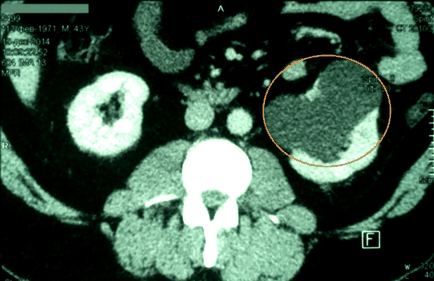

Úgy néz ki, mint egy ciszta a vese fotók

A cisztás vesekárosodás fejezhető ki több lézió a test szöveteiben, amelyek úgy néznek ki, mint egy buborék kinövések átlátszó vagy gennyes tartalom. Fent látható, úgy néz ki, mint egy ciszta a vese fotók, alatt és azt mutatják, hogy minek az alapján, hogy ezt a fajta diagnózis a diagnózis MRI, CT és az ultrahang.

Mint látható a képen, a vese ciszta befolyásolhatja a bal és jobb oldalán egy párosított szerv, attól függően, hogy a betegség típusától és annak okait.

Figyelembe véve a ciszták a vese fenti képen látható egy nagy szürke folt. Ez a hely a kijelző egy nagy cisztás test, csatlakozik a test szöveteiben.

Úgy néz ki, mint egy ciszta ultrahangra fenti képen látható összes részletet. Általában ciszták a képek jelennek meg egy közepes vagy nagy méretű foltok vagy eszméletvesztést néhány ág vagy csatornákat.

Mivel a gyenge megnyilvánulása tünetek korai szakaszában a fejlődés, vese ciszta látható csak az ultrahang-vizsgálat vagy egy tomográfiás vizsgálat.

A tumor a fejlesztési folyamatban képesek behatolni a mélyebb rétegek a veseszövet és provokál duzzanat és a kár a szomszédos szervekhez. Ez a folyamat látható a fekete pontok formájában az ultrahang képeket.